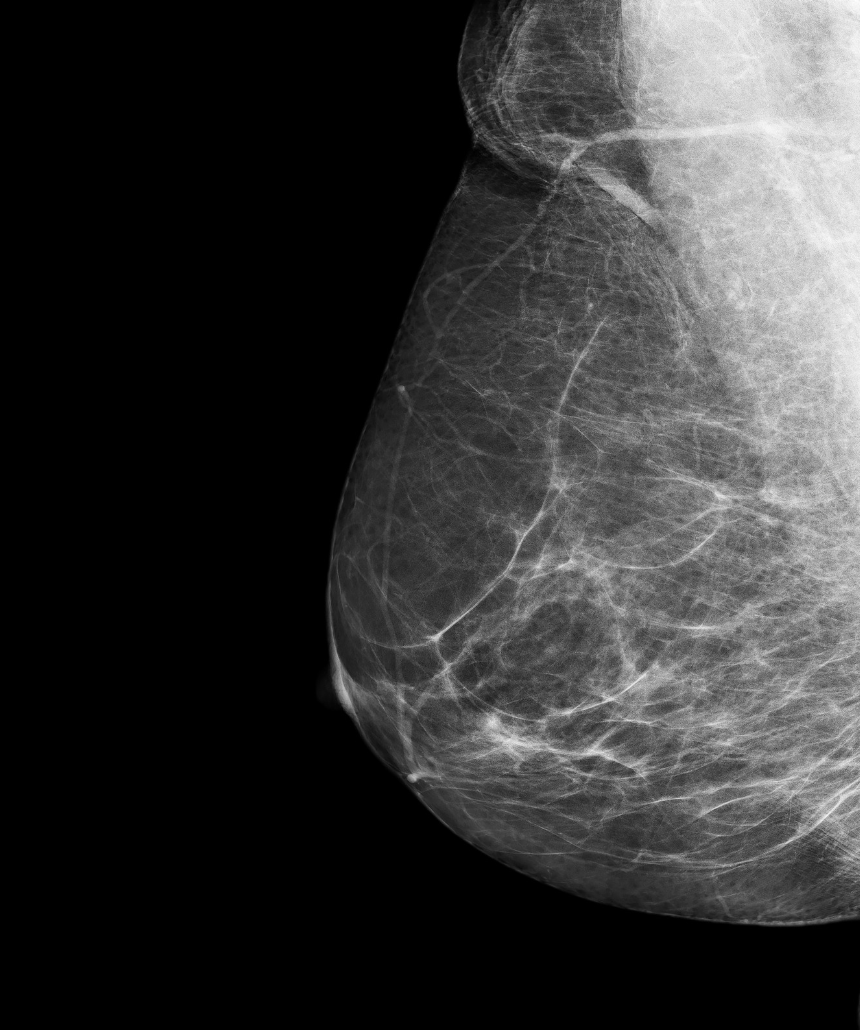

AB-MRI is an innovative breast imaging technique designed for breast cancer screening, particularly beneficial for individuals with dense breast tissue.

Abbreviated Breast MRI (AB-MRI) is a specialized imaging technique designed to enhance breast cancer detection, particularly in individuals with dense breast tissue. Unlike standard breast MRI, which involves a comprehensive examination, AB-MRI focuses on a shorter scan time while still providing critical information for diagnosis.

AB-MRI is particularly beneficial for women with dense breasts, where traditional mammography may be less effective. Dense breast tissue can obscure tumors, making early detection challenging. By utilizing AB-MRI, healthcare providers can identify cancers that might otherwise go undetected, leading to earlier intervention and improved outcomes. This technique is an important addition to breast cancer screening protocols, offering a reliable option for those at higher risk.